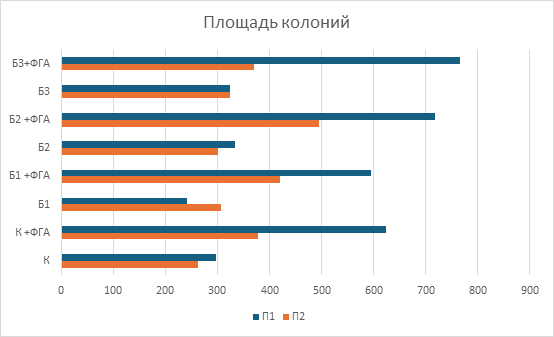

При исследовании чувствительности мононуклеарных клеток периферической крови к берберинуin vitroбыло выявлено стимулирующее влияние берберина на их пролиферативную способность, проявлявшееся увеличением количества и площади формируемых колоний. При этом благоприятный клинический исход ассоциировался не с более высокой базальной колониеобразующей активностью, а с формированием более крупных колоний, что может отражать наличие лимфоцитарных клонов с более высоким пролиферативным и метаболическим потенциалом. Это позволяет предположить, что прогностическое значение может иметь не общее число клеток, а качественные характеристики клонального пролиферативного ответа (рис.3, 4).

У пациента с благоприятным клиническим ответом изначально отмечалась более низкая базальная колониеобразующая активность МНПК: количество колоний было на 56% меньше по сравнению с пациентом с рефрактерным течением заболевания, однако их средняя площадь превышала данный показатель на 22%. Воздействие берберина в исследованных концентрациях вызывало дозозависимое усиление колониеобразующей способности МНПК у обоих пациентов, при этом наибольшая стимуляция наблюдалась при сочетанном применении берберина и фитогемагглютинина, что свидетельствует о синергическом эффекте изучаемого соединения с митогенной стимуляцией (рис.5, 6). Использование ФГА позволило оценить влияние берберина в условиях активированной иммунной реакции, что приближаетмодель in vitro к условиям реализации противоопухолевого иммунного ответаin vivo.

Кроме того, были выявлены индивидуальные различия в чувствительности МНПК к берберину: у пациента с полным ответом на терапию наибольшее увеличение количества колоний наблюдалось при концентрации 1мкмоль/л, тогда как у пациента с неблагоприятным исходом пик пролиферативного ответа смещался на 2мкмоль/л (рис.5). Полученные различия могут объясняться особенностями метаболической и пролиферативной активности отдельных лимфоцитарных клонов. Более крупные колонии у пациента с благоприятным исходом могут отражать наличие клонов с высоким метаболическим потенциалом и способностью к интенсивному клеточному делению, тогда как большее число, но мелких колоний у пациента с неблагоприятным исходом может соответствовать функционально менее активным клональным линиям.

Анализ средней площади колоний позволил оценить качественные характеристики пролиферативного ответа МНПК при воздействии берберина и его комбинаций с ФГА (рис.6). У пациента с благоприятным клиническим исходом колонии отличались более крупными размерами, что указывает на наличие лимфоцитарных клонов с высоким пролиферативным и метаболическим потенциалом. Эти наблюдения подчеркивают, что размер колонии, а не только общее количество пролиферирующих клеток может быть важным показателем функциональной активности клеточных клонов и их потенциальной способности к эффективному противоопухолевому иммунному надзору.

Рис.6. Средняя площадь образовавшихся колоний мононуклеарных клеток периферической крови при добавлении различных концентраций берберина.

К – контроль, К + ФГА – контроль + ФГА, Б1 – берберин 1мкмоль, Б1 + ФГА – берберин 1мкмоль + ФГА, Б2 – берберин 2мкмоль, Б2 + ФГА – берберин 2мкмоль + ФГА, Б3 – берберин 4мкмоль, Б3 + ФГА – берберин 4мкмоль + ФГА.

Примечание: составлен авторами по результатам данного исследования